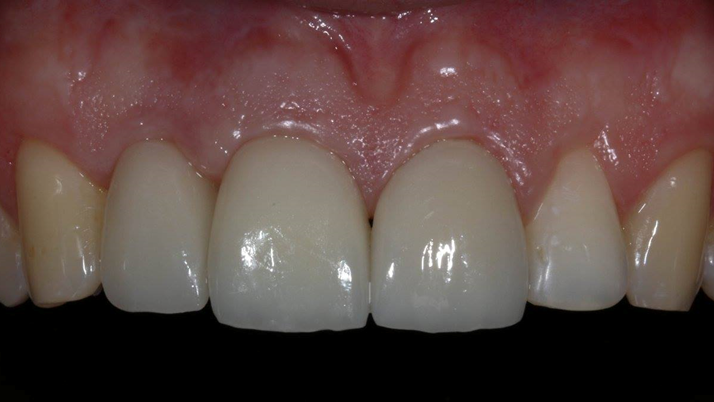

Clinical case: Patient-centered approach: treatment strategy for Root Membrane Technique & delayed implant placement

- Courtesy of Dr. Yoshiharu Hayashi, Japan -

Socket Shield Technique, anterior esthetics, maxillary anterior, esthetic, esthetics, delayed implant placement, socket preservation, AnyRidge, Root Membrane Kit, Root Membrane Technique, Partial Extraction Therapy, PET, esthetic zone, fuse abutment, Dr. Yoshiharu Hayashi,#11,#21,#22

Products:

AnyRidge implant system, fuse abutment Root membrane kit, PET Kit